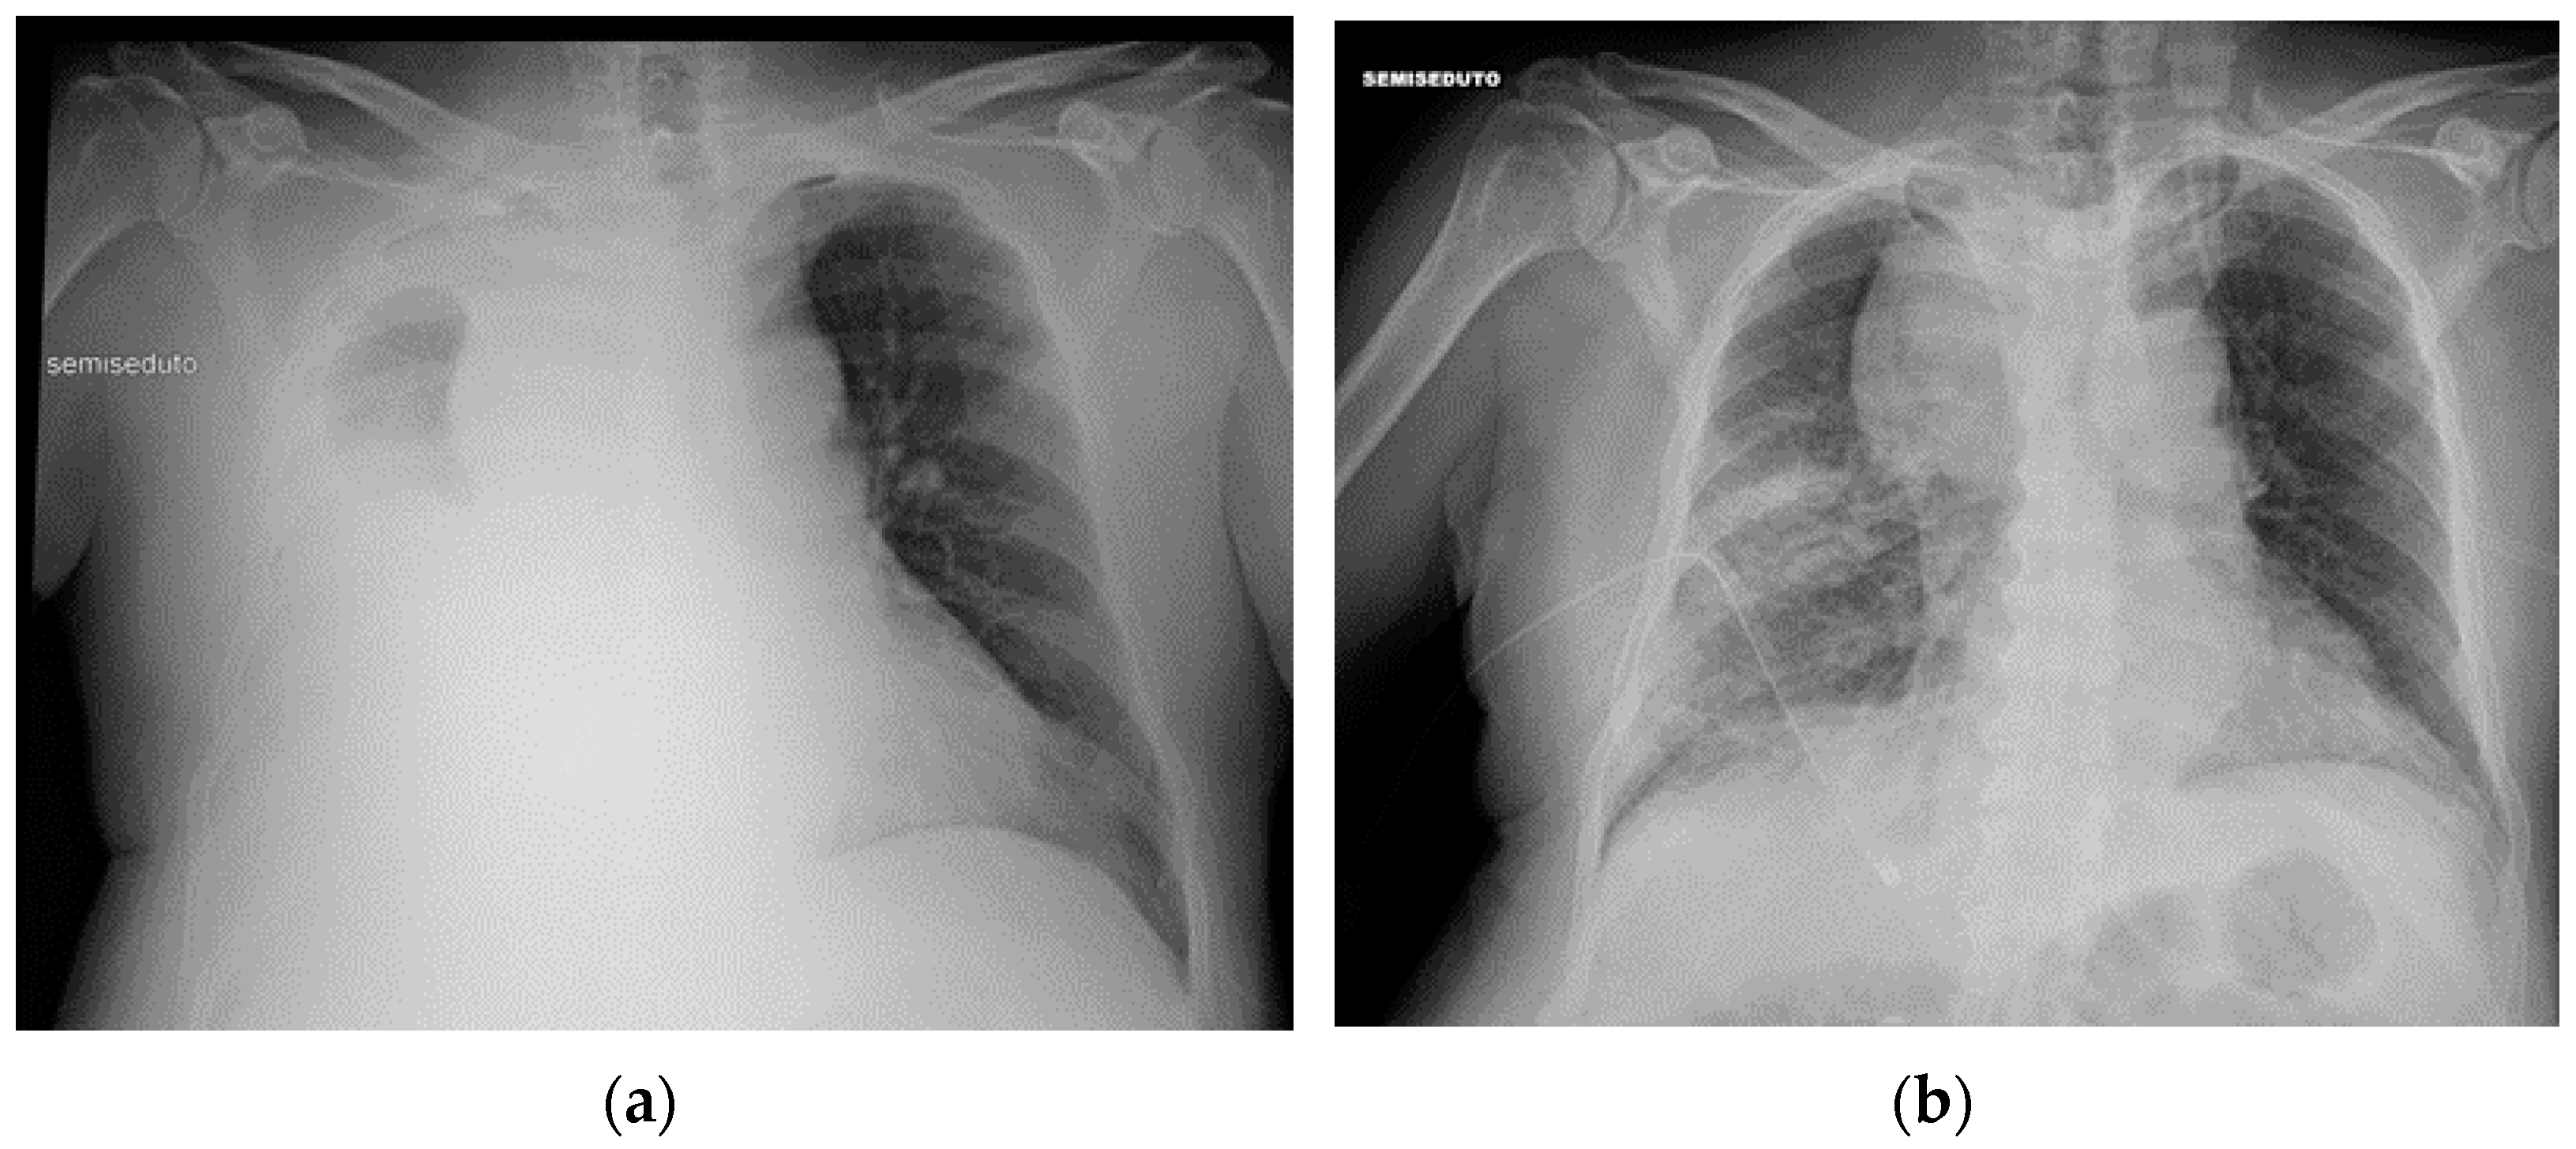

The following section discusses a series of CXRs depicting other cardiac devices that are not included in the previously mentioned ones (Figure 18, Figure 19 and Figure 20).

Figure 18.

This CXR shows the result of a transcatheter aortic valve implantation (TAVI) (green arrow). The radiogram also includes a PM, a tracheostomy tube and a right jugular CVC.